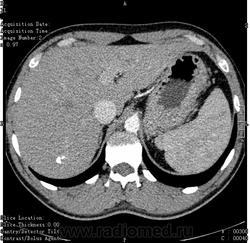

- https://radiomed.ru/sites/default/files/styles/case_slider_image/public/user/16314/ct.1.002.jpg?itok=n00uCisV

- https://radiomed.ru/sites/default/files/styles/case_slider_image/public/user/16314/ct.1.005.jpg?itok=tL-o0Zyd

- https://radiomed.ru/sites/default/files/styles/case_slider_image/public/user/16314/ct.1.006.jpg?itok=eD2B8PpJ

- https://radiomed.ru/sites/default/files/styles/case_slider_image/public/user/16314/ct.1.009_0.jpg?itok=t616c8pc

- https://radiomed.ru/sites/default/files/styles/case_slider_image/public/user/16314/ct.1.013.jpg?itok=naYfaJaK

- https://radiomed.ru/sites/default/files/styles/case_slider_image/public/user/16314/ct.1.016.jpg?itok=7QI04EsU

- https://radiomed.ru/sites/default/files/styles/case_slider_image/public/user/16314/ct.1.017.jpg?itok=EJmrsm0z

- https://radiomed.ru/sites/default/files/styles/case_slider_image/public/user/16314/ct.1.019.jpg?itok=KMCM7VHI

- https://radiomed.ru/sites/default/files/styles/case_slider_image/public/user/16314/ct.1.020.jpg?itok=m1jAA0ZW

- https://radiomed.ru/sites/default/files/styles/case_slider_image/public/user/16314/ct.1.021.jpg?itok=i89Jb3je

- https://radiomed.ru/sites/default/files/styles/case_slider_image/public/user/16314/ct.1.025.jpg?itok=UWwwyZZY

- https://radiomed.ru/sites/default/files/styles/case_slider_image/public/user/16314/ct.1.026.jpg?itok=FQfAszqG

- https://radiomed.ru/sites/default/files/styles/case_slider_image/public/user/16314/ct.1.027.jpg?itok=qJa3vYdf

- https://radiomed.ru/sites/default/files/styles/case_slider_image/public/user/16314/ct.1.028.jpg?itok=LjsabUNE

- https://radiomed.ru/sites/default/files/styles/case_slider_image/public/user/16314/ct.1.031.jpg?itok=cV37-2V6

- https://radiomed.ru/sites/default/files/styles/case_slider_image/public/user/16314/ct.1.032.jpg?itok=MrYi5Lda

- https://radiomed.ru/sites/default/files/styles/case_slider_image/public/user/16314/ct.1.033.jpg?itok=t7V0JYJY

- https://radiomed.ru/sites/default/files/styles/case_slider_image/public/user/16314/ct.1.038.jpg?itok=qu-97Yhs

- https://radiomed.ru/sites/default/files/styles/case_slider_image/public/user/16314/ct.1.039.jpg?itok=-aeLLBFV

Не понятно, вроде инородные тельца. Либо кальцинаты. Образования в печени не вижу. А какое тут может быть заключение, кроме кальцинатов? Признаков сосудистой опухоли (флеболиты) или любой иной опухоли , паразитарной кисты не вижу.

Кальцинаты в печени редкое явление. Вопрос мало изучен. Теоретически это последствие перенесенной инекции. Есть вариант, что могут метазстазы обызвествляться. Но в практике таких тотально кальцинированых метастазов не видел. Так что, если ничего не беспокоит, взять на контроль и забыть.

Ну, природа кальцинатов в печени может быть очень различна.

но вообще если они не сочетаются или не являются компонентами допонительных образований, характер которых требует уточнения, не увеличиваются при динамическом наблюдении и не находятся внутри желчных протоков - про них можно забыть.

"Although a wide variety of causes of hepatic calcification has been described (Table 1), the most common causes are calcified granulomas and hydatid cysts, followed by calcification as- sociated with hepatic neoplasms (3). Other ori- gins of calcification include vascular and biliary causes. "